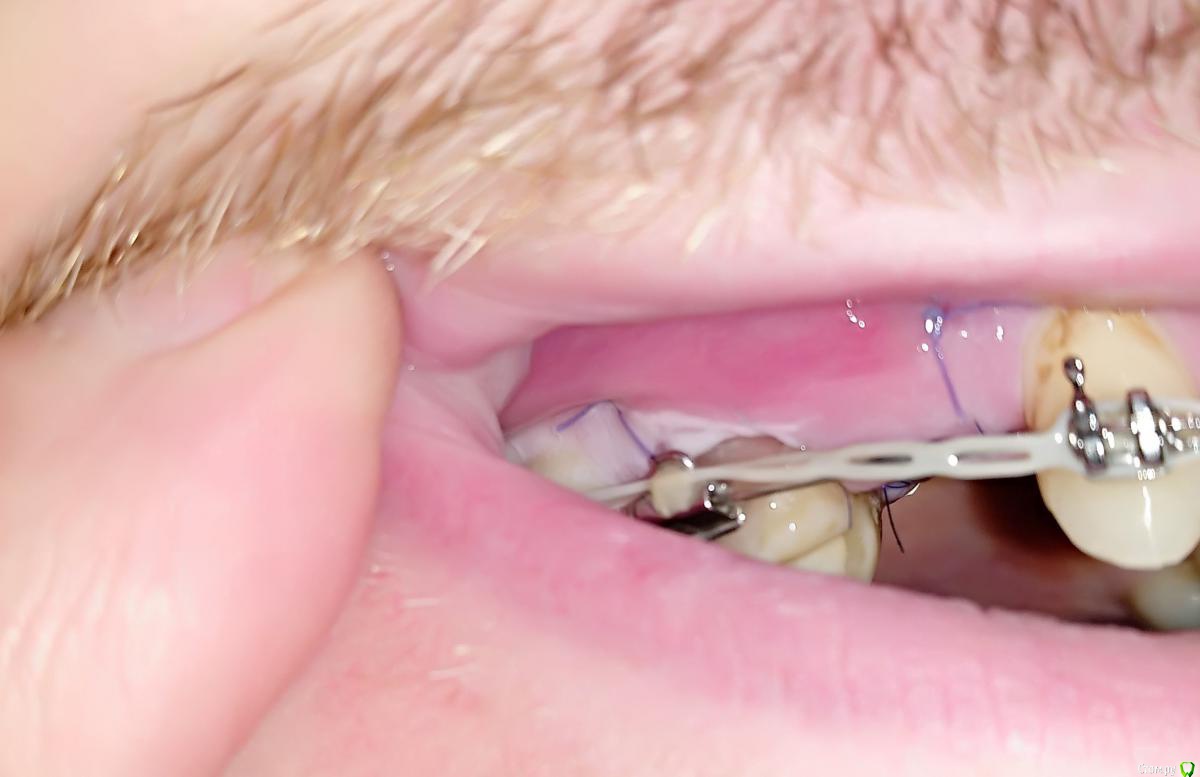

Al..ks Опубликовано 2 июня, 2019 Поделиться Опубликовано 2 июня, 2019 Прошла 30 мая имплантация 14 (3,5*9 Astra + заглушка - торк слабый. Изначально планировался сразу формирователь, но этот вариант мне больше по душе) + подсаживали десну к 16 (снимки КТ чуть позже добавлю). Пил сумамед, немисил (гадость походу - кишки крутило с него), лоратадин - три дня. Сейчас только ванночки хлоргексидина (хотя хирургическая щетка лежит с 12тыс щетинками, но забыл когда ей пользоваться начинать) Была слегка припухлость - на сегодня начала спадать остался только желтый синяк (как его побыстрее свести?)Вопрос по десне я правильно понимаю, что в районе швов это фибриновый налет? А вокруг 16-17 это тоже самое или пора панику наводить? Спасибо за ответы Ссылка на комментарий